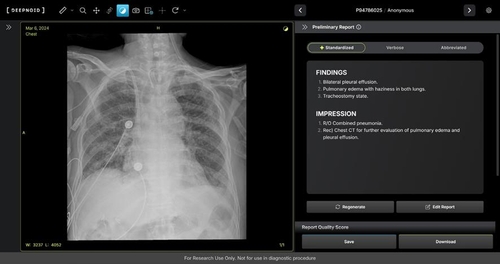

M4CXR은 흉부 X-ray 영상에서 41종의 병변을 판독해 수 초 만에 일관성 있고 신뢰성 높은 판독소견서 초안을 작성한다.

이는 흉부 X-ray 영상과 대응되는 1천만 건 이상의 판독소견서 데이터를 학습해 구현된 기술로, 응급상황에서 의료진이 예비 판독 결과를 즉시 받을 수 있어 중요한 임상 결정과 환자 진료에 더욱 집중할 수 있도록 지원하고 영상의학과 전문의의 판독을 보조한다고 회사가 전했다.